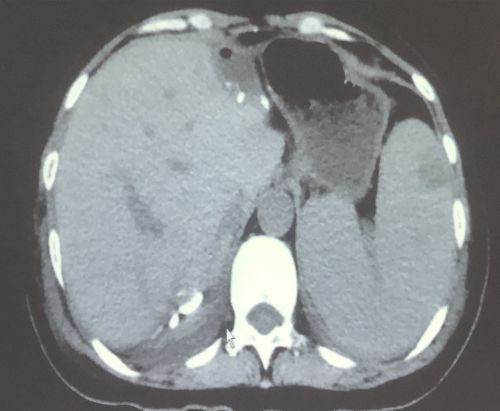

治疗前影像显示:肠道内有肿瘤(红圈内)。